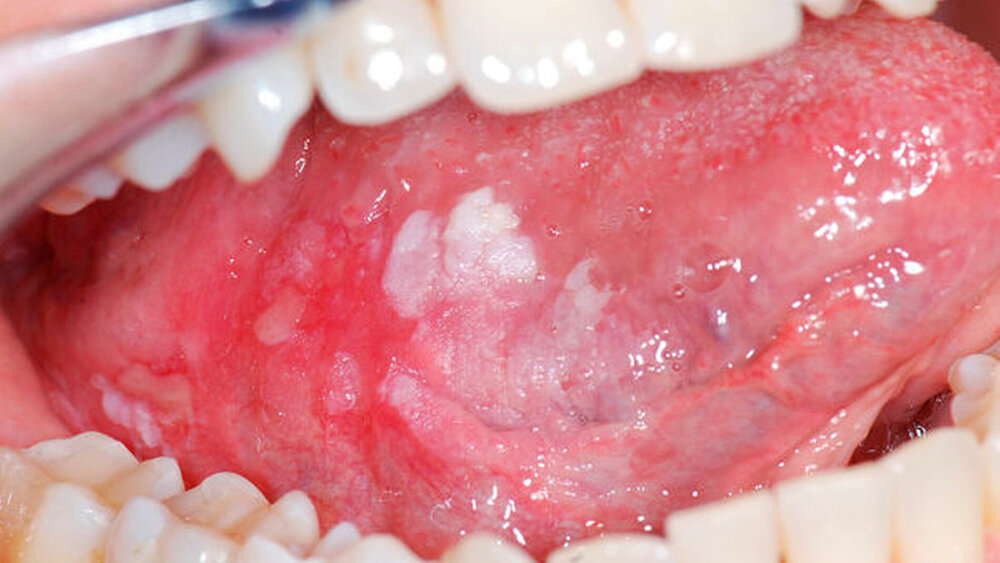

Definition der „verdächtigen“ Läsion

Da die Handlungsempfehlungen unter anderem darauf basieren, dass eine Schleimhautläsion als „verdächtig“ gewertet wird, wurden zur Konkretisierung neben dem zeitlichen Verlauf klinische Kriterien in die Leitlinie aufgenommen, die bereits bei der Erstuntersuchung als Hinweise auf eine maligne Transformation zu werten sind.

Dies sind im Einzelnen:

neu aufgetreten oder von unbekannter Dauer

starke Hyperkeratose

Inhomogenität

Erosion

Blutung bei Berührung oder leichter mechanischer Belastung

fehlende Ursache

pathologische Gefäßerweiterung/ Gefäße